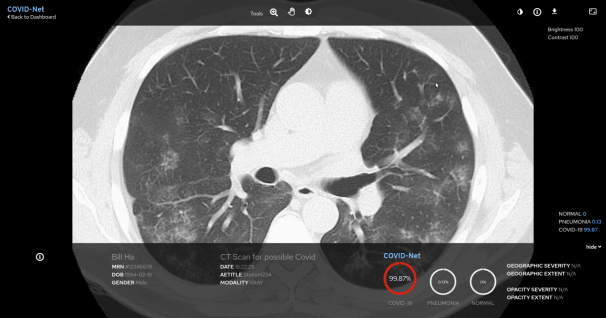

Red Hat, leverancier van open sourceoplossingen, kondigen een samenwerking aan om de implementatie van COVID-Net bij ziekenhuizen en andere zorginstellingen te versnellen. Deze suite van

Het doel van deze samenwerking is om het voor clinici makkelijker te maken om COVID-Net in ziekenhuizen te gebruiken door middel van een webgebaseerde grafische gebruikersinterface (GUI). Deze wordt met behulp van

Red Hat OpenShift - een enterprise Kubernetes-platform dat implementaties binnen complexe hybride en multicloudinfrastructuren ondersteunt - bovenop het

Boston Children's ChRIS-framework aangeboden.